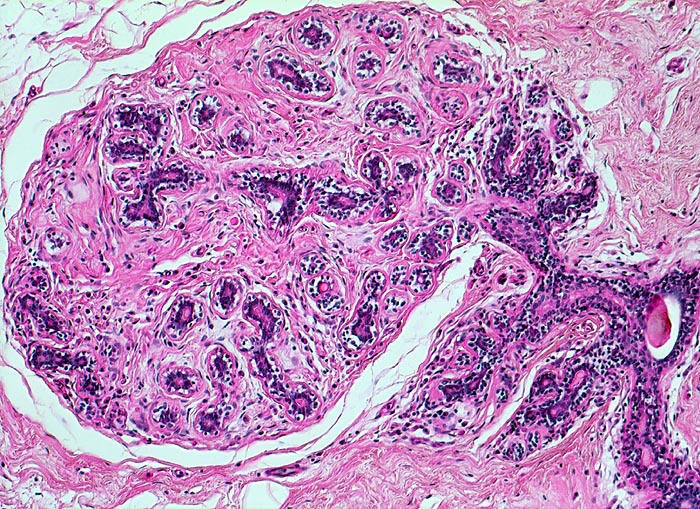

Makroskopisch bildet das mastopathisch veränderte Parenchym weisse kompakte fibröse Areale mit Einschluss von Zysten, welche oftmals eingedicktes Sekret enthalten. Neben einer Stromafibrose und zystisch ausgeweiteten Gängen mit Sekretretention findet sich oft eine unterschiedlich ausgeprägte intraduktale Proliferation von luminalen und basalen Epithelzellen. Nicht selten liegen als Begleitbefund kleine Fibroadenome, eine sklerosierende Adenose oder Gänge mit apokriner Metaplasie vor. Oftmals finden sich auch intraduktale Mikroverkalkungen. Die duktale Hyperplasie ist im Gegensatz zur atypischen Hyperplasie und zum Carcinoma in situ charakterisiert durch eine bunte, ungeordnete Proliferation ungleich grosser polygonaler bis spindeliger Zellen mit Ausbildung von schlitzförmigen Hohlräumen oder dünnen epithelialen Brücken. Die euchromatischen Kerne variieren in Grösse, Form und Lagerung. Bei paralleler Lagerung der Kerne entsteht der Eindruck eines Strömens und Fliessens der Zellen. Das duktale Carcinoma in situ ist von gutartigen intraduktalen Epithelproliferationen abzugrenzen aufgrund seiner Monomorphie (> 5185), Hyperchromasie der Zellkerne und starrer geometrischer Muster (runde scharf begrenzte wie ausgestanzte Lumina (> 5184), breite Brücken und Bögen, Mikropapillen). Eine intraduktale Epithelproliferation mit Atypie wird dann diagnostiziert, wenn nur ein Teil der Gänge oder Läppchen die typischen Veränderungen eines Carcinoma in situ zeigt. Die Abgrenzung der atypischen Hyperplasie von der Hyperplasie ohne Atypie erfolgt aufgrund qualitativer Merkmale und die Abgrenzung der Hyperplasie mit Atypie vom Carcinoma in situ aufgrund quantitativer Merkmale.

• In der Mitte rechts einige Gänge mit gewöhnlicher intraduktaler Epithelhyperplasie ohne Atypie: Polymorphe, sich überlagernde spindelige Zellen. Fliessende Anordnung der Zellen. Schlitzförmige und irregulär geformte Lumina.

• Rundlicher blauvioletter Mikrokalk in den Azini benigner Drüsenläppchen.

• Alle Drüsen zeigen eine erhaltene äussere abgeflachte Myoepithelschicht mit hellem Zytoplasma.